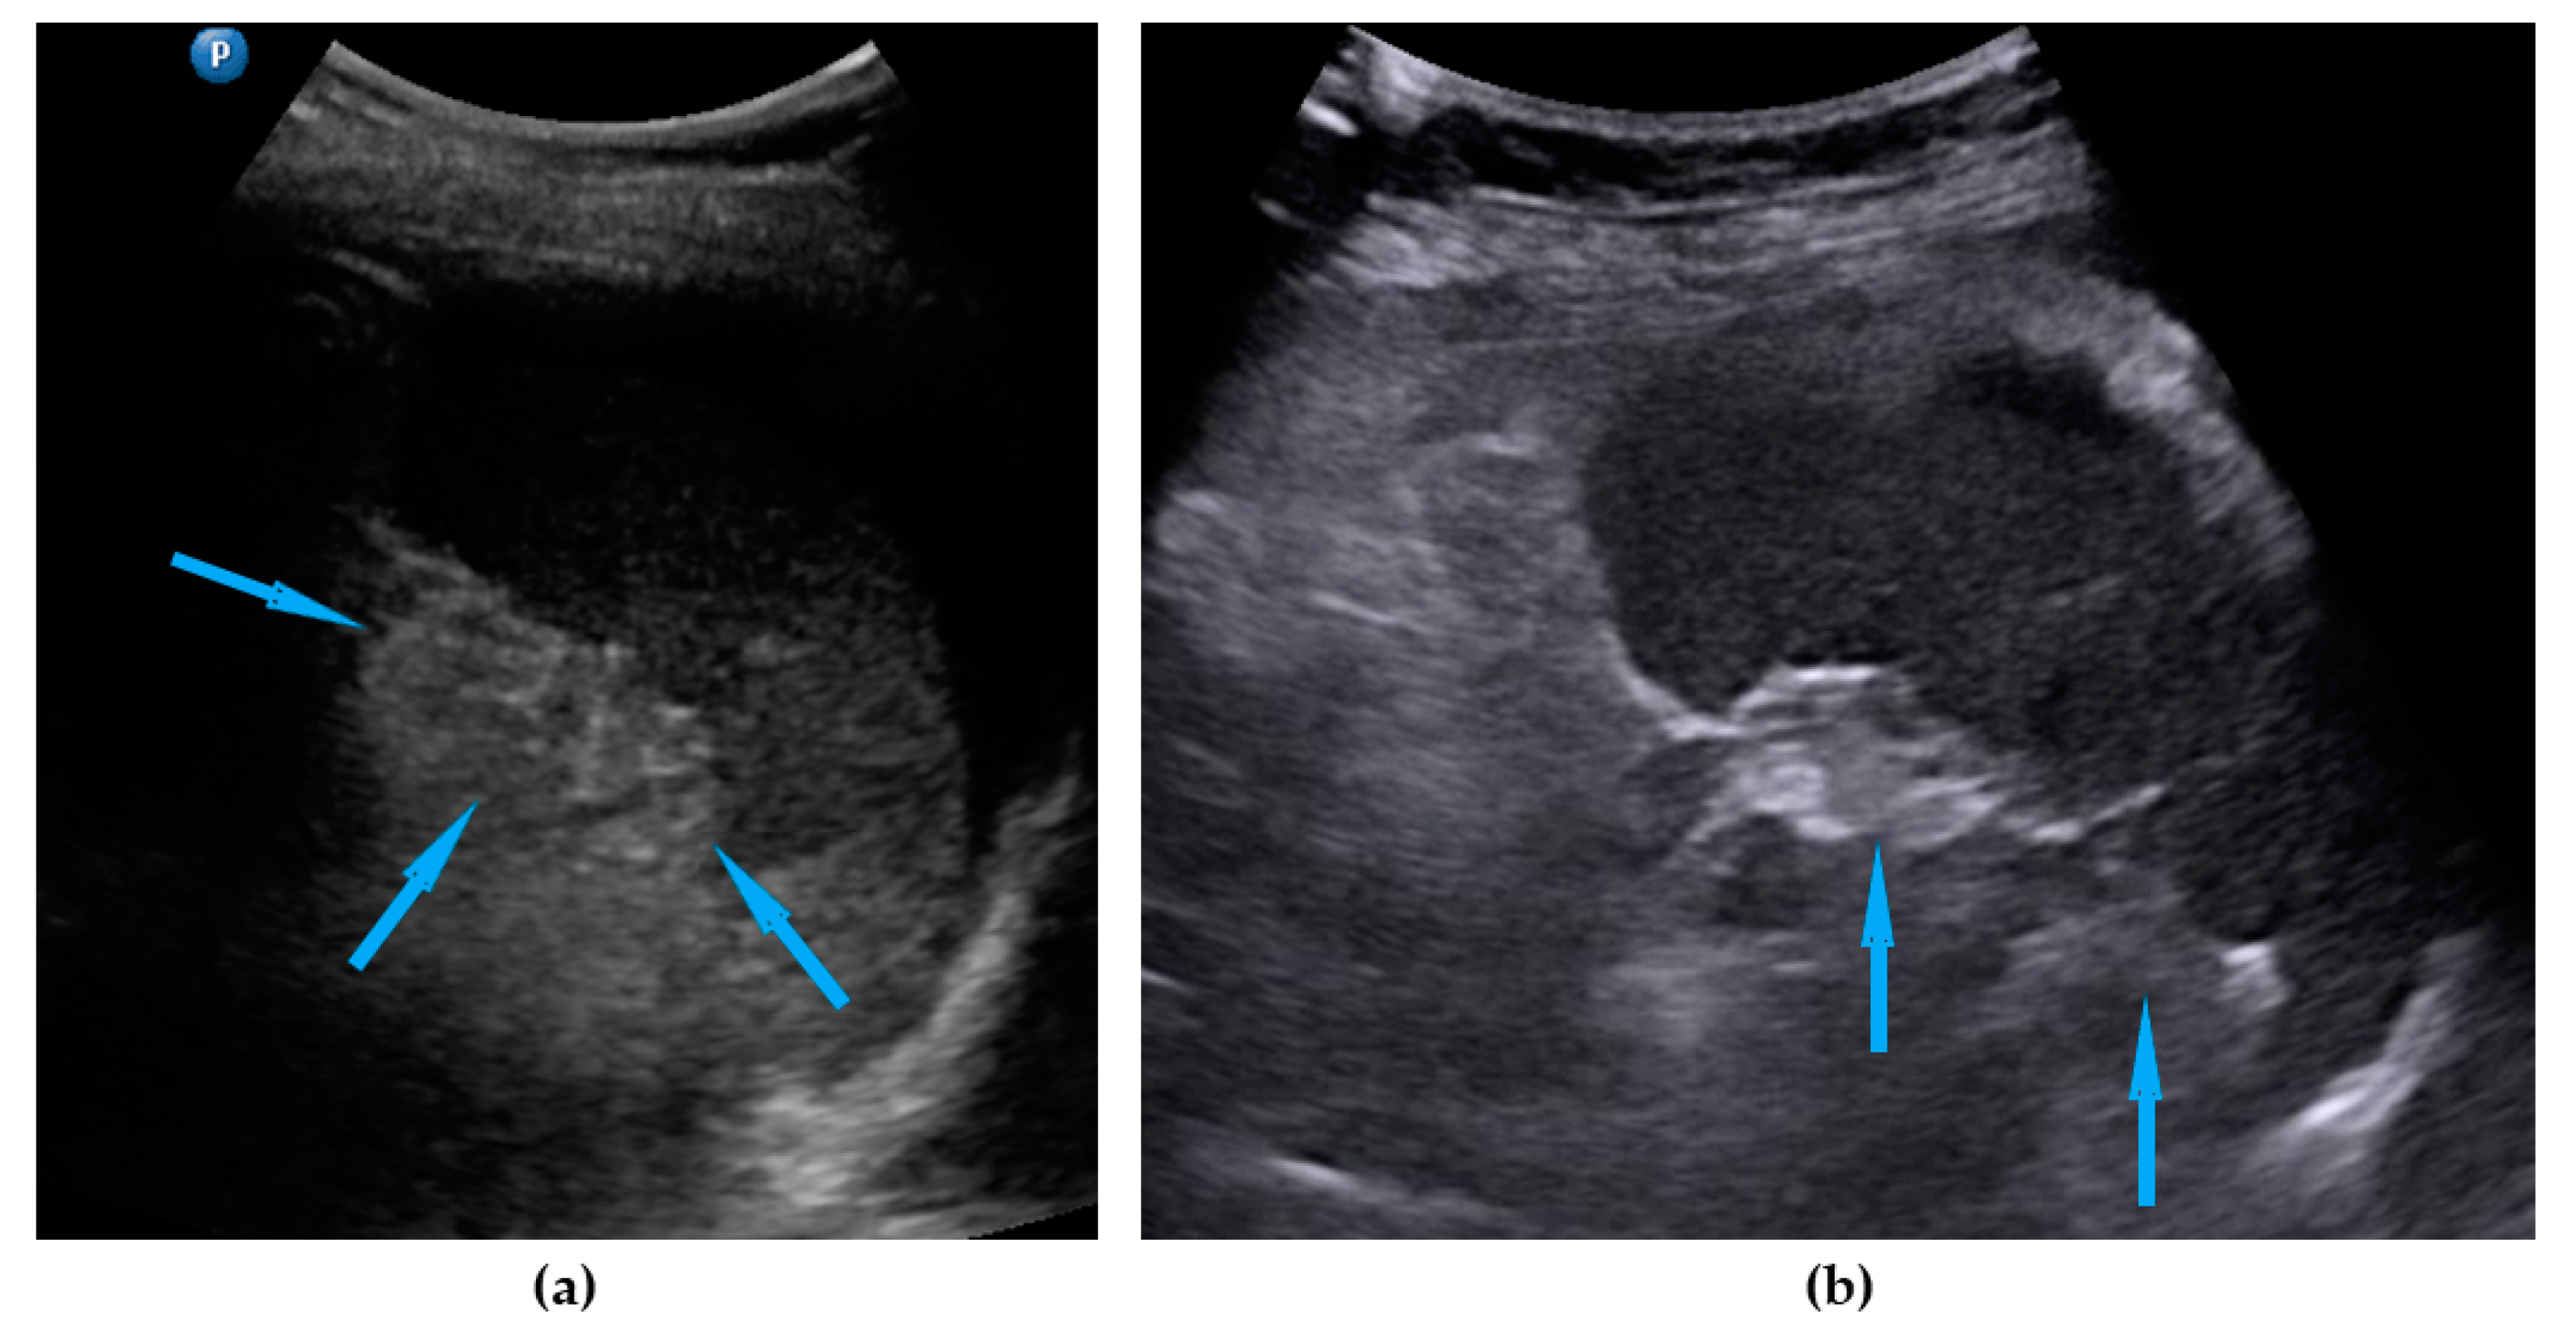

| Peritoneum, abdomen | Abdomen carcinomatosis manifest as hypoechogenic lesions over the peritoneal surface of the paracollic gutters or internal abdominal wall. | Figure 3 | Video S3 |

| Peritoneum, pelvis | Pelvic carcinomatosis manifests as hypoechogenic lesions over the peritoneal surface of the pelvic wall: laterally, in the pouch of Douglas (no rectum involvement) or the bladder in the uterine serosa. | Figure 4 | Video S4 |